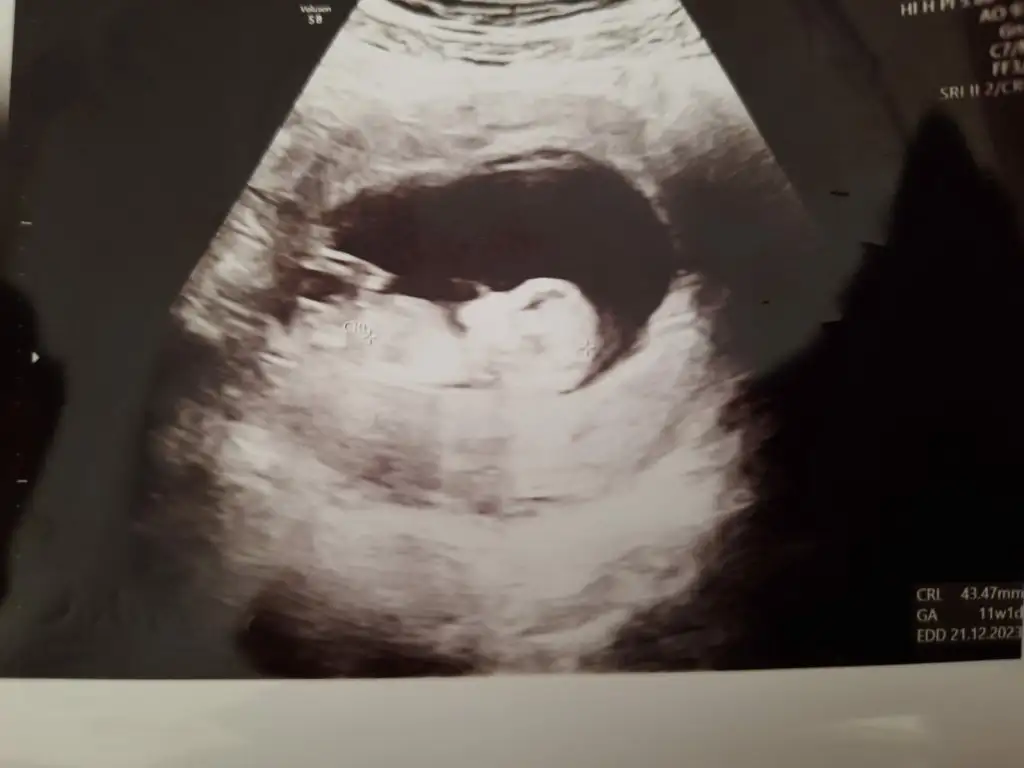

Nub teorisine göre kız görünüyor

Nub’a göre yorum yapmak için bacak arasında nub kısmının görünmesi gerek. Yukarıdaki görüntüde diğer kızların pipi dediği şey nub. Bu teoriye göre nub yere paralelse kız, havaya doğru açı yapıyorsa erkekmiş. Sizde o kısmı göremediğimden yorum yapamadım

Ya aslında iyi biliyorum ama kendimde olunca kuşkuya düştüm bir an tahminim oğlum da tutmuştu nuba göre bakalım bunda da nuba göre kız gördüm belki bilen başkası olursa diye paylaşıyorum bu cumaya tekrar gidecem bakalimAmin hepsi sağlıklı olsun bebişlerimizin, cinsiyeti de merak ediyor tabi insan. Ben de çok sabırsızım. Tüm teorileri araştırdımbelki içimizde cinsiyeti belli olanlar nub teorisi tutmuş mu diye bize yorum yapabilir

Görünen nub ise kız gibi :) sağlıklı oldunTeoriye göre benim ki belli mi? Yani bir tahmin ?